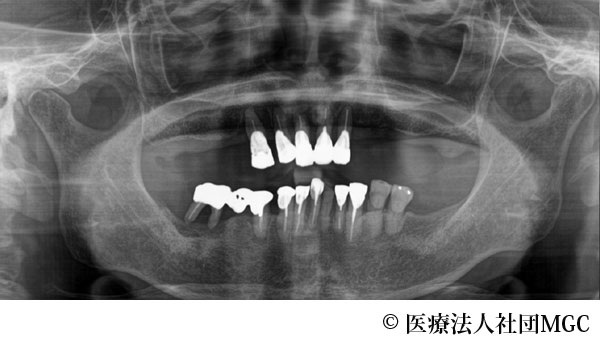

【症例1】上下All-on-4(オールオンフォー)

- 治療前

- 治療後

- 治療名

- 上下All-on-4(オールオンフォー)

- 費用

- 5,915,800円(税込)

- 期間

- 8ヵ月

治療内容

患者様の症状

歯がボロボロで食事が困難であるとご来院されました。

治療法

ご相談の結果、患者様の生活の質(QOL)を向上させ、しっかり噛めるように上下All-on-4(オールオンフォー)を行いました。

治療結果

機能性、審美性ともに改善し、満足していただけました。

※治療結果は患者様によって個人差があります。

治療を行う上での注意点(リスク・副作用)

インプラント周囲炎の可能性、まれに歯が欠ける可能性があります。